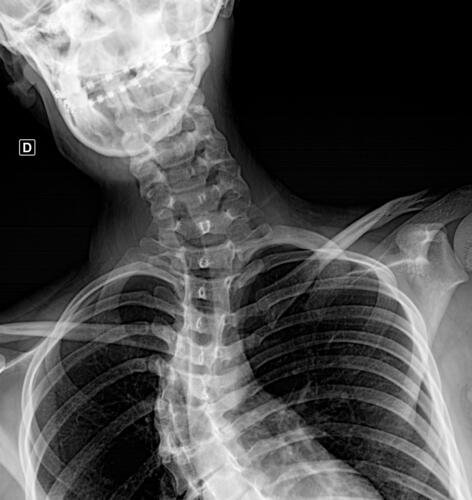

A Vá tem 13 anos e precisa urgentemente realizar uma cirurgia na coluna.Valentina foi surpreendida com o diagnóstico de escoliose hepática grave com 67 graus de desvio (desvio longitudinal da coluna), e precisa realizar com urgência a cirurgia corretiva, os exames foram realizados em Porto Alegre, mas a cirurgia está marcada para dia 13/07 em São Paulo devido a gravidade do caso, para isso a família terá que ficar residindo próximo ao hospital em São Paulo por no mínimo 30 dias para uma plena recuperação. Sabemos bem que qualquer procedimento cirúrgico é delicado, na coluna então nem se fala.Após o diagnóstico e o prognostico dessa doença a família se desfez de alguns bens (carro e moto) para cumprir os prazos dos exames e consultas, necessitando agora arrecadar o valor para a estadia da pequena Valentina e seu pós operatório (medicação, consultas e fisioterapia).

Em anexo os exames (laudo e imagens) para expressas a gravidade do caso.